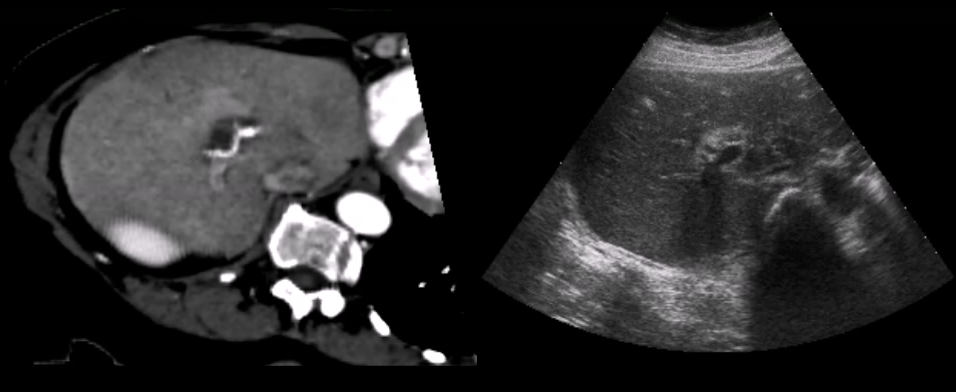

Nikas et al. published an evaluation of the application of co-registered 2D ultrasound and MRI for intra-operative navigation nikas03 . Ultrasound based navigation shows promising results due to live acquisition at high frame rates and easy portability. For prostate brachytherapy a combination of ultrasound and co-registered CT can be used, as shown by Fuller et al. fuller05 . Existing commercial products apply optical tracking for intra-operative navigation during neurosurgery sonowand11 . Figure 5 shows how ultrasound and MRI can be blended together into a single reference frame burns07 .

Refer to caption

(a)

(b)

Figure 5: Registering ultrasound and MRI, se Figure (a), enables advanced visualization techniques to provide a better structural overview burns07 , as shown in Figure (b).